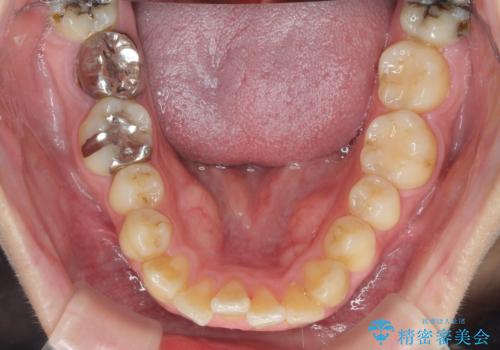

歯を抜かずに行う前歯の角度の改善

- 歯を抜かずに前歯の角度を改善したい、と矯正治療を希望され来院されました。

可及的に前歯部にIPR(歯間の削合)を行い、抜歯をせずマウスピース矯正システムインビザラインで歯の排列を行っていく治療計画としました。

治療の前後を比べると、がたつきや歯の角度が改善したことがしっかりと確認されました。